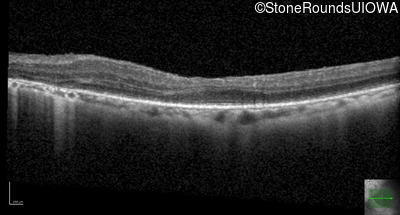

This 30 year old woman has had poor vision in her right eye for her entire life and first noticed decreased vision in dim light and constricted fields in her left eye in middle school. She had surgery in infancy for "short gut syndrome" and had liver transplantation at age 3. She also has a history of pulmonary stenosis, scoliosis, and ataxia.